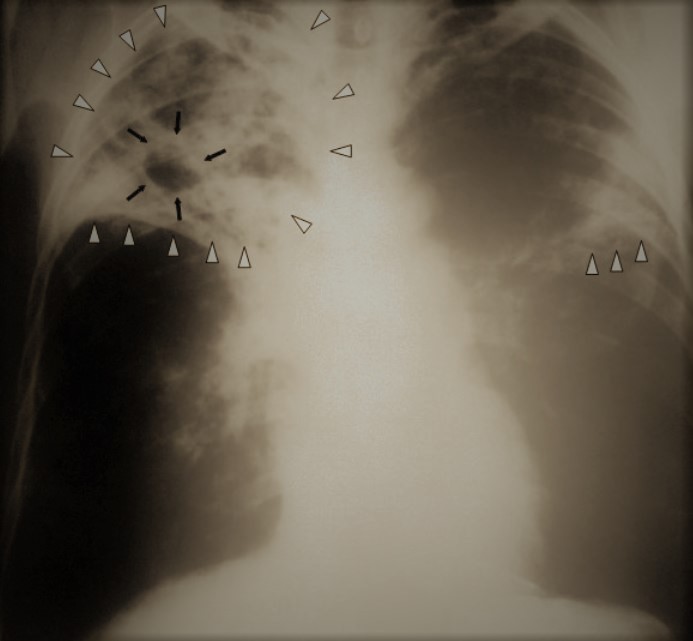

Even though previously proof was dismissed , his hypothesis was that injecting of live tuberculosis bacilli into subjects , the bacilli would function as a vaccine. Another aspect of his experiment was based on the Nazi racial theory that race played a factor in developing tuberculosis.

By proving his theory he injected live tuberculosis bacilli into the lungs and bloodstream of 20 Jewish children, at the Neuengamme concentration camp.